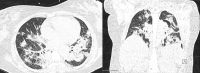

There are few cases of pregnant women with novel corona virus 2019 (COVID-19) in the literature, most of them with a mild illness course. There is limited evidence about in utero infection and early positive neonatal testing. A 41-year-old G3P2 with a history of previous cesarean deliveries and diabetes mellitus presented with a 4-day history of malaise, low-grade fever, and progressive shortness of breath. A nasopharyngeal swab was positive for COVID-19, COVID-19 serology was negative. The patient developed respiratory failure requiring mechanical ventilation on day 5 of disease onset. The patient underwent a cesarean delivery, and neonatal isolation was implemented immediately after birth, without delayed cord clamping or skin-to-skin contact. The neonatal nasopharyngeal swab, 16 hours after delivery, was positive for severe acute respiratory syndrome-coronavirus 2 (SARS-CoV-2) real-time polymerase chain reaction (RT-PCR), and immunoglobulin (Ig)-M and IgG for SARS-CoV-2 were negative. Maternal IgM and IgG were positive on postpartum day 4 (day 9 after symptom onset). We report a severe presentation of COVID-19 during pregnancy. To our knowledge, this is the earliest reported positive PCR in the neonate, raising the concern for vertical transmission. We suggest pregnant women should be considered as a high-risk group and minimize exposures for these reasons. KEY POINTS: · We report a severe presentation of COVID-19 in pregnancy requiring invasive ventilatory support.. · This is a case of positive RT-PCR in first day of life, suggesting possible vertical transmission.. · There were no detectable maternal antibodies for COVID-19 until after delivery..

Figures